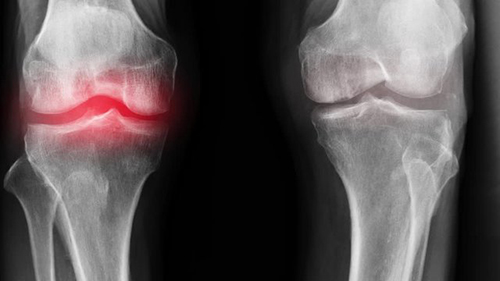

- ข้ออักเสบ

- ข้อเสื่อม